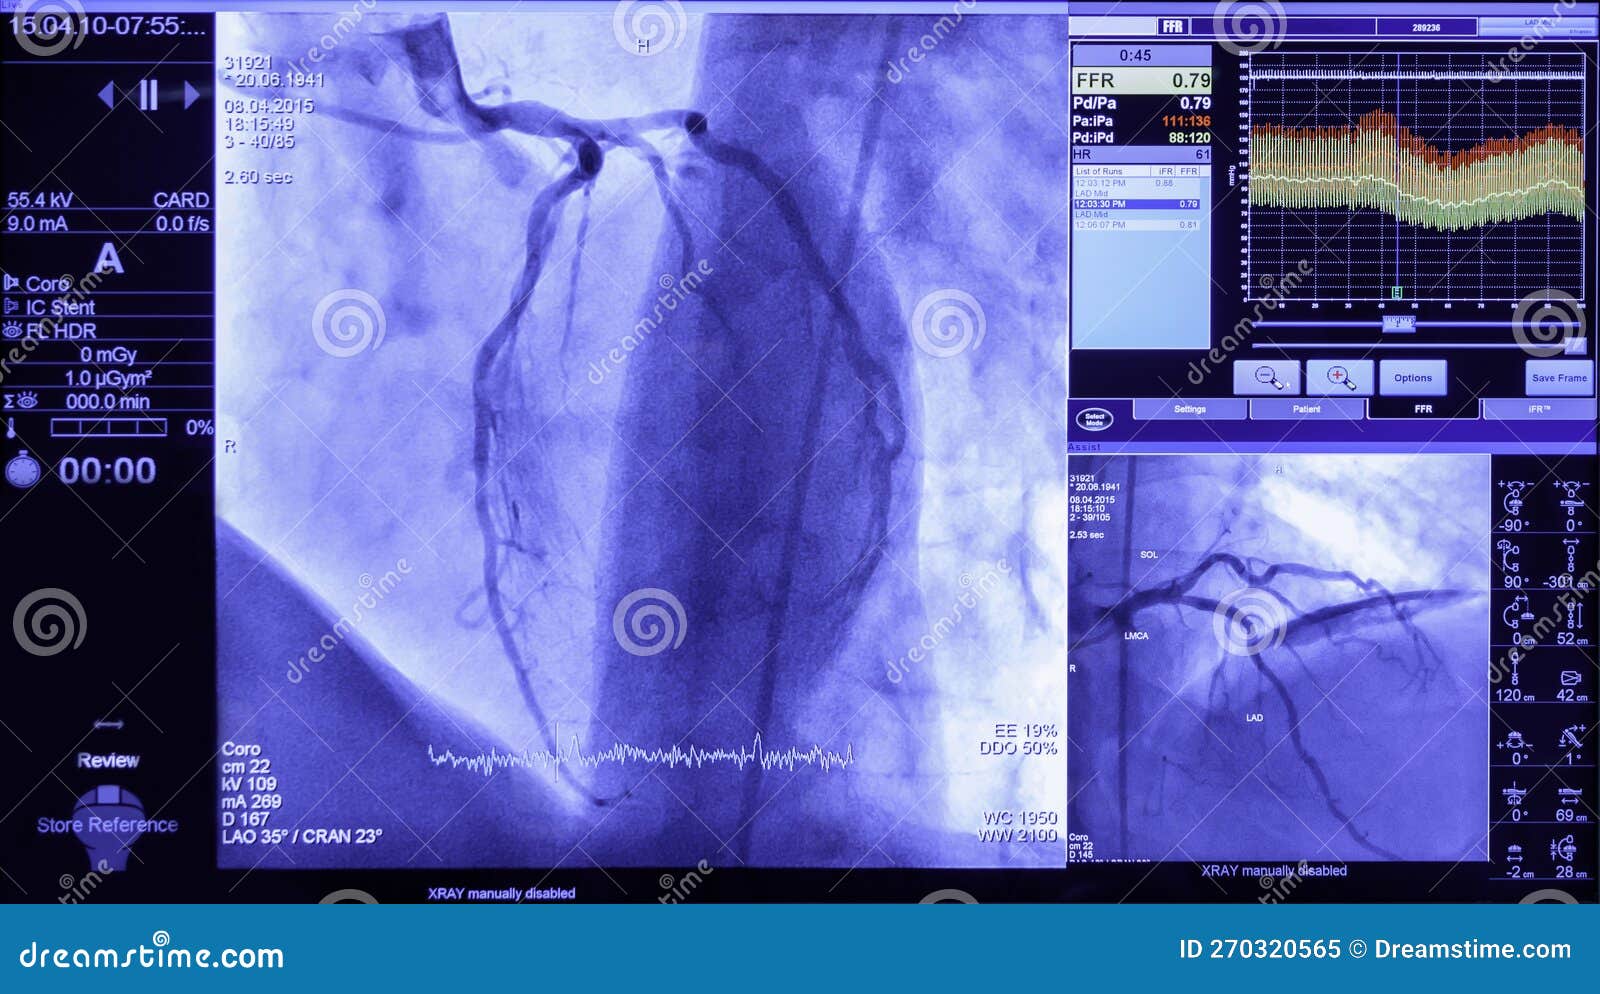

From www.dreamstime.com

Projection of Veins on the Screen in Heart Surgery, Transcatheter Heart Catheter Surgery Risk [3]although there are minor risks,. The most common risks of cardiac catheterization include bleeding or hematoma. Cardiac catheterization is a medical procedure that cardiologists, or heart specialists, use to evaluate heart function and diagnose cardiovascular conditions. A cardiac cath is generally safe. What are the risks of cardiac catheterization? Rare risks include reaction to contrast dye, impaired kidney function due. Heart Catheter Surgery Risk.